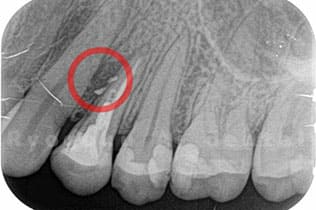

STEP 2

- レントゲン検査

- レントゲン写真にて、問題となっている歯牙の状態を確認します。

根の治療にて治る見込みがない場合や歯が割れている場合は抜歯となります。 -